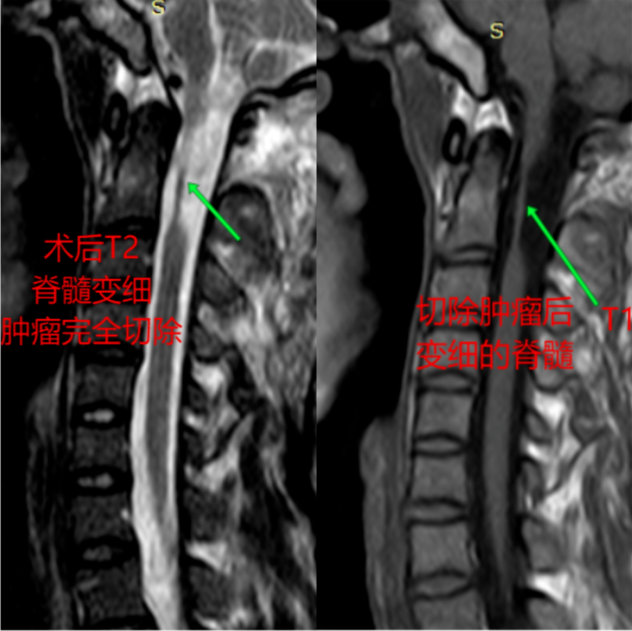

经人传说,昭通市第一人民医院神经外科擅治肿瘤,年轻的他带着对生命的眷念来我院神经外科就诊,经行颈椎MRI提示C1-2椎管内外位占位巨大肿瘤,再经专科查体发现,他右手精细活动差(只能用勺,不能持筷子);右侧肢体较左侧纤细,右侧下肢肌力3级、余肢体肌力4+级,左上肢肌张力正常,右上肢及双侧下肢肌张力增高。桡反射、膝反射、踝反射亢进,生理反射存在,病理反射巴氏征及霍夫曼征阳性。

(术后)

经精心准备手,患者手术很成功。肿瘤切片,病理诊断为神经节细胞瘤。一切都在预料之中。

患者术后恢复良好,经康复治疗,现已逐渐脱离拐杖,独自行走。